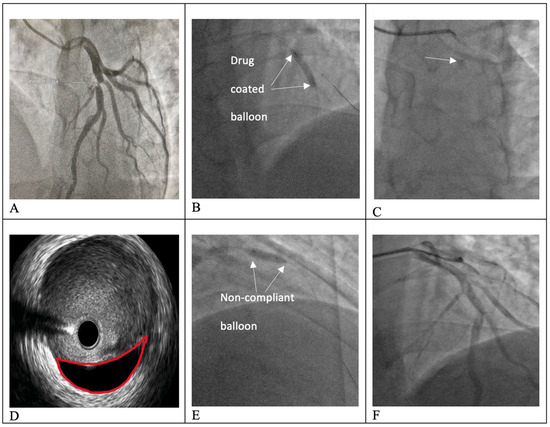

The Middle Meningeal Artery (MMA) occupies a pivotal role in the pathophysiology of migraine, functioning as a vascular and neuroimmune interface that precipitates the characteristic pulsatile pain. The inhibition of this pathophysiological cascade has been investigated as a therapeutic strategy. However, fewer than a dozen centers globally have disseminated procedural or mechanistic data. Given the nascency of this field and the imperative for standardization, the present review synthesizes mechanistic and clinical evidence underpinning intra-arterial pharmacological modulation of the MMA for migraine management. Methods: A focused narrative review was undertaken, drawing upon select but influential studies from pioneering research groups investigating intra-arterial interventions targeting the MMA. The extant literature was thematically categorized and organized according to the loci of cascade interruption and their corresponding clinical outcomes. Results: Since 2009, intra-arterial therapies for severe headache syndromes have evolved, initially utilizing nimodipine for vasospasm-related headaches, progressing to verapamil for reversible cerebral vasoconstriction, and more recently, lidocaine for refractory or status migrainosus, occasionally in conjunction with MMA embolization. Contemporary research uses language that conceptualizes migraine as an immunologically mediated neurovascular disorder, as opposed to a purely vascular or neuronal entity. Recent investigations have identified interleukins such as Interleukin-1β, Tumor Necrosis Factor-α, and Interleukin-6 as critical amplifiers of trigeminovascular activation. Purinergic signaling through the P2X3 receptor and the P2Y13 receptor, in conjunction with pituitary adenylate cyclase-activating polypeptide and vasoactive intestinal peptide pathways, has been implicated in the modulation of MMA excitability and neuropeptide release. The development of novel calcitonin gene-related peptide receptor antagonists, such as zavegepant, further substantiates the artery’s significance as a pharmacological target. Conclusions: These findings support a shift toward immune-modulating intra-arterial therapeutic strategies, with migraine interventions targeting cytokine and neuroimmune signaling within the MMA, rather than relying exclusively on vasodilatory mechanisms.